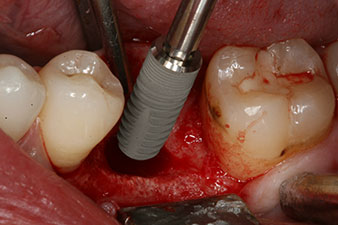

Sechs Wochen nach Extraktion zeigte sich jedoch nach Präparation des Mukoperiostlappens im Bereich der ehemaligen mesialen Alveole eine unvollständige Ossifikation.

Nach gründlicher Entfernung des Granulationsgewebes wurde das Implantat wie geplant eingebracht (blueSky, bredent).

Das Drehmoment beim maschinellen Einbringen war 43 Ncm. Zusätzlich wurde, nach Einschrauben eines speziellen, auf das Implantatsystem abgestimmten Mess-Pfostens (SmartPeg), der ISQ-Wert mit der Sonde des W&H Osstell ISQ Modul bestimmt.